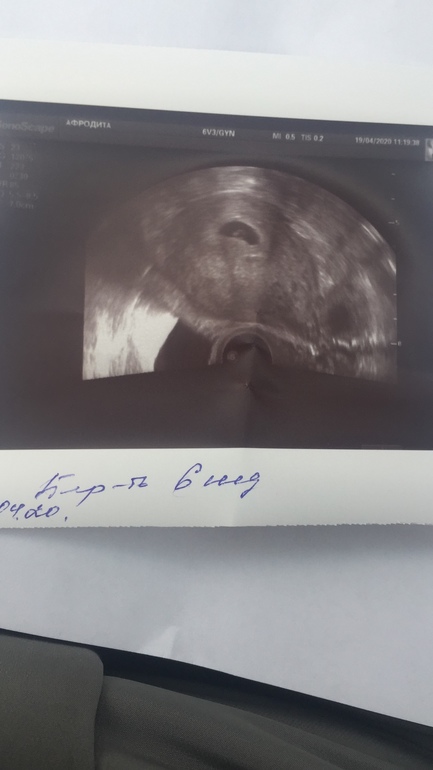

Нашли бусинку)

Изменения и болезни во время БНаписала пост не в то сообщество)В общем все хорошо, первые замеры видимо не верные.Пя 16 мм Ктр 3,4Сб +Жм 6 мм